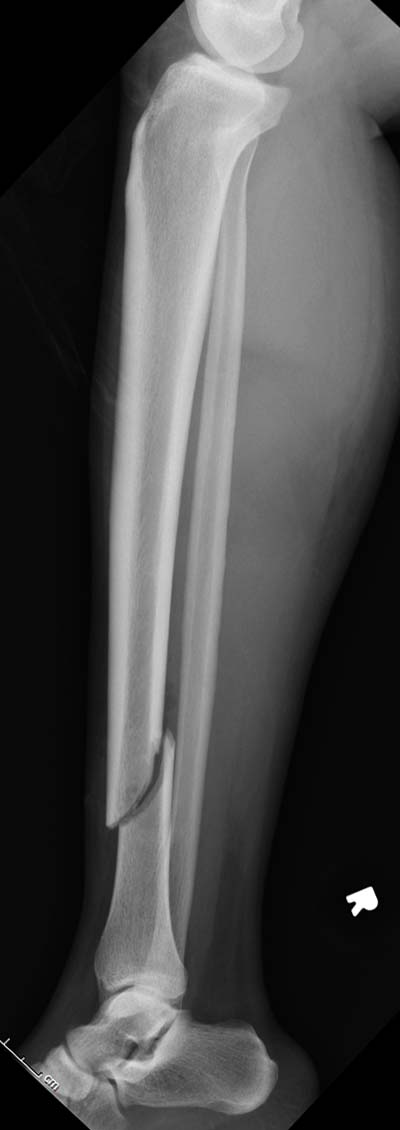

Здесь несколько снимков изолированного перелома большеберцовой с

интактной малоберцовой.  Weber clamp, блокирующие спицы и риминг в

центре канала отрепонировал перелом....